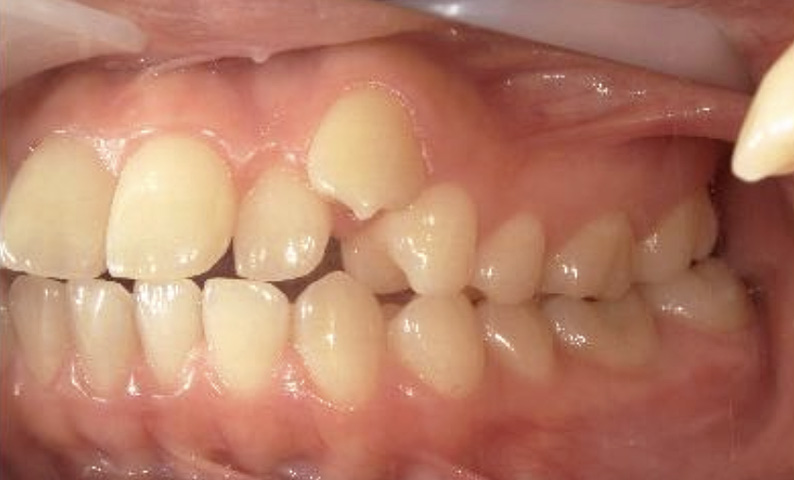

症例_025 上下顎の部分矯正

治療期間:13ヶ月金額:51万円+税女性前歯のガタガタ出っ歯

| Before | After |

|---|---|